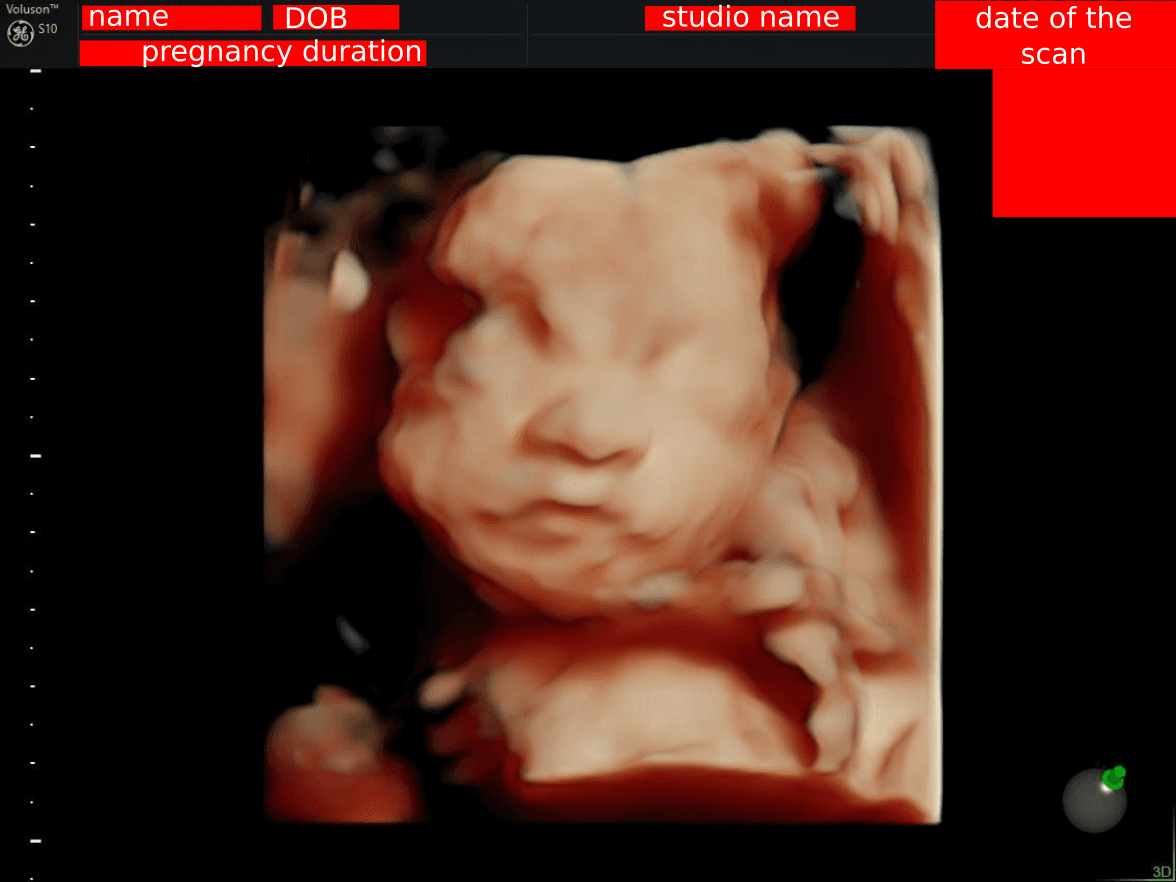

When you get a 3D ultrasound, you often receive a screenshot of the ultrasound machine's screen, like this:

Example of an uncropped ultrasound scan showing personal information

This image includes:

• Your name

• Date of birth

• Pregnancy duration

• Studio name (which can hint at your location)

• Date & time of the scan

Sharing the full image can be risky due to identity theft concerns.

This FREE tool allows you to safely crop the image, focusing only on the ultrasound itself: